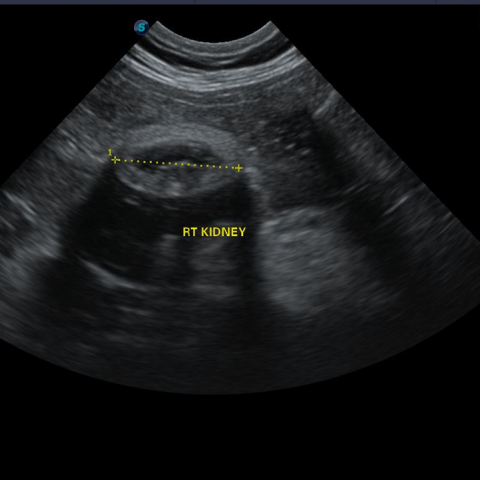

Ϋ≈άεάΚ ΩλΗ° Ηωά« ≥κΤσΙΑάΜ ΝΠΑ≈«œΑμ «ςΨ–ΑϋΗ°,άϊ«ς±ΗΜΐΦΚ,»ΘΗΘΗσ ±’«ϋ ά·ΝωΩΓ ΑϋΩ©«œ¥¬ Η≈Ωλ ΝΏΩδ«― άε±βά‘¥œ¥Ό. ΒΕΦΚΙΑΝζ ΦΖΟκ, ≥κ»≠, ΗΗΦΚΝζ»· Βν Ω©Ζ·ΑΓΝω ΩχάΈΩΓ ά««Ί Ϋ≈άεά« ±β¥…ΩΓ Ι°ΝΠΑΓ Μΐ±φ Φω ά÷Ϋά¥œ¥Ό. ΫΡΜγΖ° Α®Φ“, ΟΦΝΏΑ®Φ“, ±Η≈δ≥Σ Φ≥Μγ Βν Κώ Τ·άΧάϊάΈ ΝθΜσάΧ ≥Σ≈Η≥ΣΙ«ΖΈ, ά”ΜσΝθΜσ ΗΗ άΗΖΈ¥¬ Ϋ≈άεΚ¥άΜ Τ·ΝΛ Νΰ±β ΨνΖΝΩωΦ≠ ΡΓΖαΫΟ±βΗΠ ≥θΡΓ¥¬ ΑφΩλΑΓ Η≈Ωλ ΗΙΫά¥œ¥Ό. Ϋ≈άεΚ¥άΧ ΗΗΦΚ»≠ Β«Ηι ¥ΌΫΟ ΝΝΨΤΝω±β ΨνΖΤ±β ΕßΙ°ΩΓ ΝΕ±βΩΓ ΙΏΑΏ, ΝΕ±β ΡΓΖαΑΓ Η≈Ωλ ΝΏΩδ«’¥œ¥Ό.

Ϋ≈άε«ςΨΉΑΥΜγ(BUN, CREA, P, άϋ«ΊΝζ), SDMA(Ϋ≈άε Ω©Αζά≤ ΑΥΜγ), «ςΨ–, Ωδ ΑΥΜγ, ΚΙΚΈ Ο άΫΤΡ ΑΥΜγΗΠ ≈κ«Ί Ϋ≈άεΚ¥ ¥ήΑηΗΠ Νχ¥ή«’¥œ¥Ό.

ΒΕΦΚΙΑΝζάΜ Η‘ΨζάΜ Εß, ±Η≈δ≥Σ Φ≥ΜγΑΓ ΝωΦ”Β… Εß, ¥ΌάΫ ¥Ό¥Δ ΑΓ ά«Ϋ…Β… Εß, Α«Α≠ΑΥΝχ «“ Εß, ΗΕΟκ άϋ ΑΥΜγ ΫΟ ΝΛΙ–ΑΥΜγΖΈ Ϋ≈άεΑΥΜγΗΠ Νχ«ύ«’¥œ¥Ό.